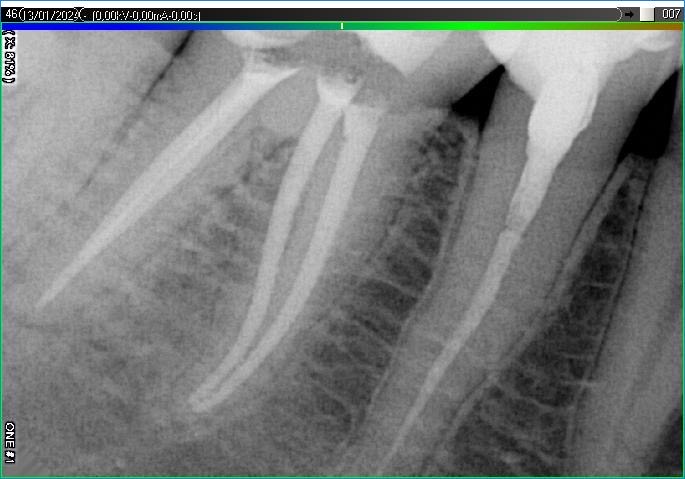

Вилучення інструменту з каналів зуба